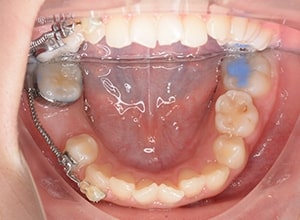

| 口腔内所見 | over jet 3.5mm,over bite4.0mm、下顎正中右側偏位2.0mm、大臼歯関係は左側Ⅰ級であったが、右下6は右下E早期喪失のため近心傾斜しておりⅢ級の臼歯関係となっていた。また上下顎前歯は軽度の叢生を呈していた。 |

| パノラマ所見 | 右下5は右下6近心傾斜により萌出部位不足が認められた。上下顎8歯胚が確認できた。 |

| 批評・予后 | 右下5及び7の萌出前に右下6を整直させることによって、右下5の自然萌出が可能となり正常咬合への咬合誘導が行えたと思う。 |